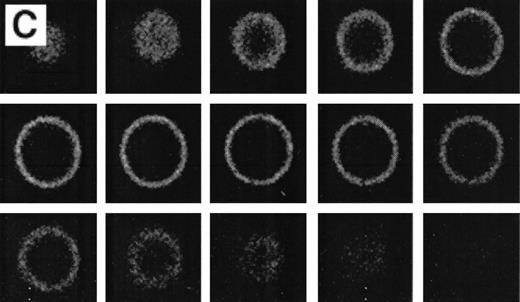

Because the number of positive cells in the thalassemic RBC samples was low, the population was enriched in AV-FITC–positive cells by magnetic bead separation as described before.15 After separation, the cells were washed with calcium-free buffer, which removed all of the AV-FITC/magnetic bead complex from the cells. These RBCs were reincubated in AV-FITC in the presence of calcium to visualize the distribution of PS on the membrane surface. These unfixed AV-FITC–labeled RBCs were then studied by CSOM, and optical sections taken at 0.5 μm cuts were made when indicated (Fig 4). When it was necessary to simultaneously analyze the distribution of PS on the red cell surface and α-globin deposits on the cytosolic site of the membrane, AV-FITC–labeled cells were lightly fixed, permeabilized, and incubated with the murine monoclonal anti–α-globin antibody, followed by Texas-Red–labeled goat antimurine immunoglobulin antibody.17 18

RBCs from a thalassemic patient (HbE/β-thalassemia, splenectomized) enriched from the population labeled with AV-FITC using magnetic beads coated with an FITC antibody (see the Materials and Methods section). (A, B) Typical cells labeled with AV-FITC in the native unfixed state and then analyzed by serial optical sections in confocal fluorescent microscopy. Panel A shows the equatorial section of a cell homogeneously labeled with AV-FITC. Panel B shows three equatorial sections of a cell heterogeneously labeled with AV-FITC. (C,D) RBCs initially labeled with AV-FITC in the unfixed state and then labeled with monoclonal anti–α-globin chain antibody, and secondary Texas-Red–labeled goat antimurine antibody. This double-labeled cell was then analyzed by fluorescent microscopy. The areas where Texas Red (red) and FITC (green) overlap are yellow.

Figure 4 shows representative fields of RBCs from a splenectomized patient with HbE/β-thalassemia PS exposing RBCs, enriched by magnetic bead separation, relabeled with AV-FITC, and analyzed by CSOM, showed two patterns of fluorescence. Approximately half of the AV-FITC–labeled thalassemic RBCs show a smooth rim fluorescence over the entire membrane (Fig 4A), similar to normal cells with a scrambled membrane (Fig 3). However, in other RBCs the AV-FITC membrane fluorescence was more heterogeneously distributed. In addition to a rim fluorescence, sites with increased fluorescence were observed, indicating that PS was enriched in these areas (Fig 4B). Interestingly, these AV-FITC–labeled sites at the surface of the cell were localized to areas that seemed to bulge over an inclusion body as shown in the equatorial cut of such labeled cells shown in Fig 4B. Because this patient had severe β-thalassemia intermedia, it was logical to suppose that the inclusion was a membrane associated deposit of excess α-globin chains, which we tried to confirm using the monoclonal antibody to denatured α-globin chains shown by Texas-Red–labeled antimurine immunoglobulin.

The equatorial cut (midsection) of such labeled cells showed the enrichment of Texas Red in distinct areas, indicating that denatured α-globin chains were localized in domains adjacent to the membrane, confirming results reported before.18 When such RBCs were analyzed for both AV-FITC (green) and anti–α-globin/Texas-Red (red), fluorescence microscopy showed a bright-yellow fluorescence in dual-color analysis, indicating that both AV-FITC and the Texas-Red label were enriched in the same membrane regions (Fig 4B and C). In contrast, the cells that labeled homogeneously with AV-FITC did not label with Texas Red. These data strongly suggest a colocalization of denatured α-globin chains and PS in the same area.

The labeling with AV-FITC allows identification of individual cells that expose PS by fluorescent microscopy. AV-FITC binds to the outer surface of cells that have lost their normal phospholipid asymmetry as indicated by CSOM analysis. Those cells that have lost their membrane integrity (ghosts) are brightly labeled due to the fact that AV-FITC has access to the PS in the inner monolayer. AV-FITC can be removed from intact red cells by a simple wash in calcium-poor buffer, a further indication that the FITC-labeled 38 kD protein has only access to the outer surface of the cell. In order to increase the number of AV-FITC–positive cells in the thalassemic red cell population to make analysis by fluorescent microscopy more feasible, we used a technique that selects these cells by magnetic bead separation.15Analysis after renewed labeling of unfixed RBC with AV-FITC shows at least two types of PS exposure in thalassemic red cells. On the one hand, a similar labeling is found (Fig 4A) as with normal red cells scrambled with calcium and ionophore as shown in Fig 3C. In these cells, uniform rim fluorescence indicates a uniform distribution of PS on the outer surface. Other cells showed enhanced domains of PS on the surface of the thalassemic red cells (Fig 4B). The underlying mechanism for these hot spots is not clear. These data suggest that the normal maintained asymmetry of the PL bilayer can be disrupted locally. However, based on the rapid diffusion rates of phospholipids in the plane of the bilayer before AV-FITC labeling, one would not expect these domains in the case of unrestricted movement of PS on the surface of the cell. Hence, this would lead to the conclusion that PS movement is restricted in the plane of the bilayer of these cells confining PS to local areas that are identified by AV-FITC labeling. Although the concept of lipid domains as the result of restricted movement has been hypothesized, few reports have been able to indicate such regions.

Interestingly, in RBCs that had been labeled with AV-FITC in the native unfixed state and then lightly fixed and permeabilized, antibodies against α-globin chains colocalize with AV-FITC (Fig 4C and D), leading to similar pictures as found with AV-FITC labeling of intact unfixed cells (Fig 4B). These data suggest that in some cases PS is enriched on the outer surface in areas of α-globin chain accumulation. It was recently reported that endogenous red cell AV is found in regions where Heinz bodies attach to the plasma membrane,21 thereby suggesting that PS was enriched in these areas in the inner monolayer. Membrane skeletal proteins including spectrin22 and a band 4.1,23 24 have been shown to interact with PS. A change in the distribution or lipid/protein interaction of these proteins could be involved in the local accumulation of PS. However, the underlying mechanism is not known at present.